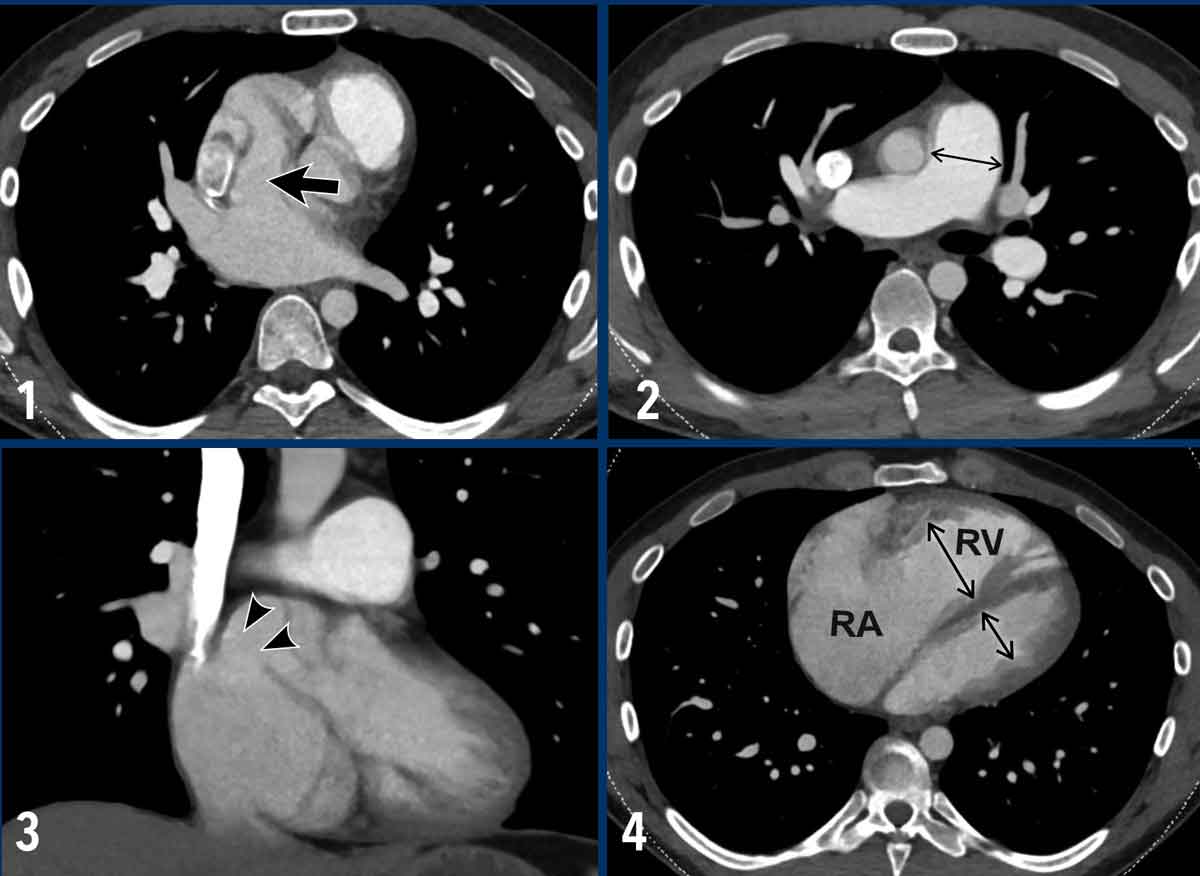

Images

1. There is an abnormal communication between the left atrium and the superior cavo-atrial junction (arrow).

2.  Dilatation of the pulmonary artery.

3. Coronal reconstruction demonstrating the abnormal communication between the left atrium and the superior cavo-atrial junction (arrowheads).

4. Severe dilatation of the right atrium and ventricle due to the left-to-right shunt.